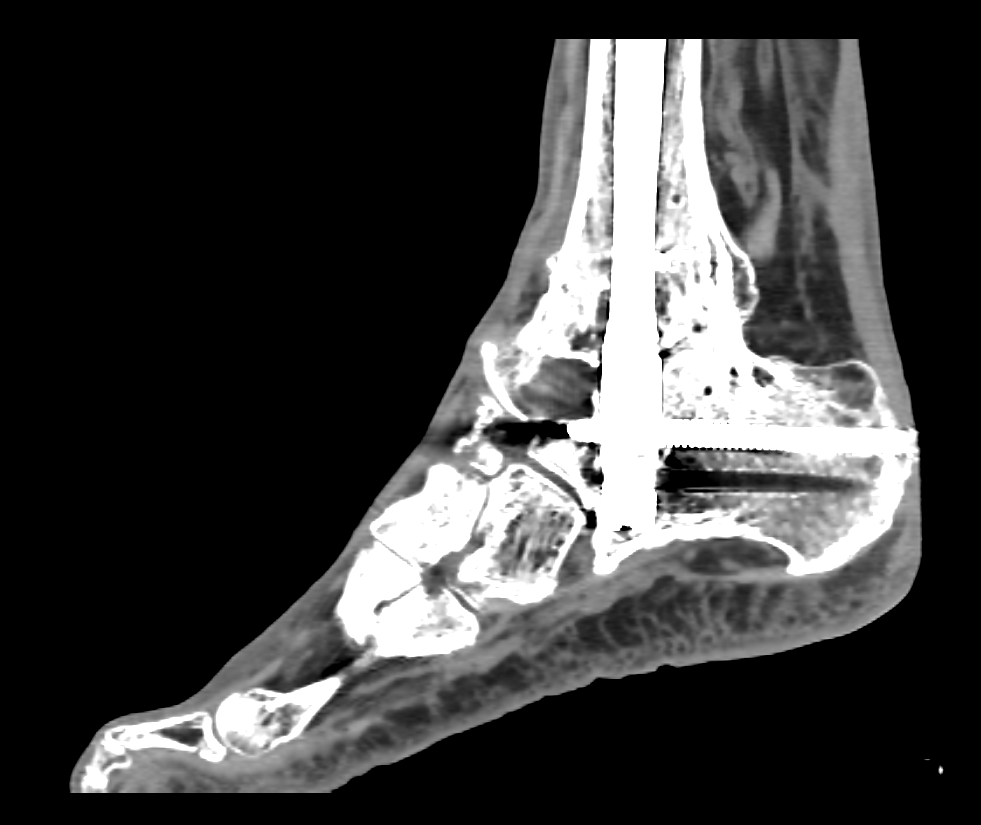

La impresión 3D ha tenido gran acogida en trauma y ortopedia por ser una gran ayuda para entender la relación entre todos las estructuras y para planear las cirugías.

Este es el caso de un pie que había sufrido un trauma y ya había sido intervenido, pero querían hacer otra cirugía para corregir los resultados después de un periodo de curación.

Mediante el uso de segmentación médica se pudo extraer la información del tejido oseo y corregir los artefactos de las imágenes medicas.